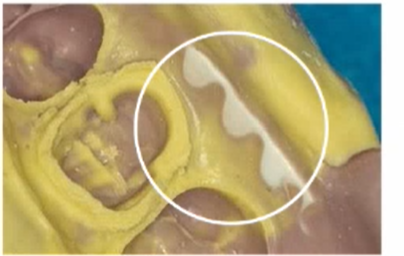

Delamination

Caused by exceeding working time or material being stored in elevated temperature